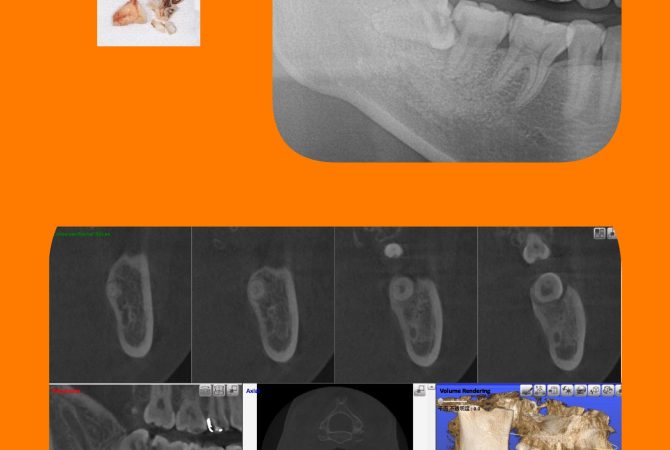

2026.1.31 イベント院内のこと ☆バレンタインイベント☆ 詳しく見る 2026.1.28 症例 横向き親知らずの抜歯症例 詳しく見る 2026.1.14 症例 EMS社エアフローを使用した定期検診症例 詳しく見る 2026.1.4 症例 横向き親知らずの抜歯症例 詳しく見る